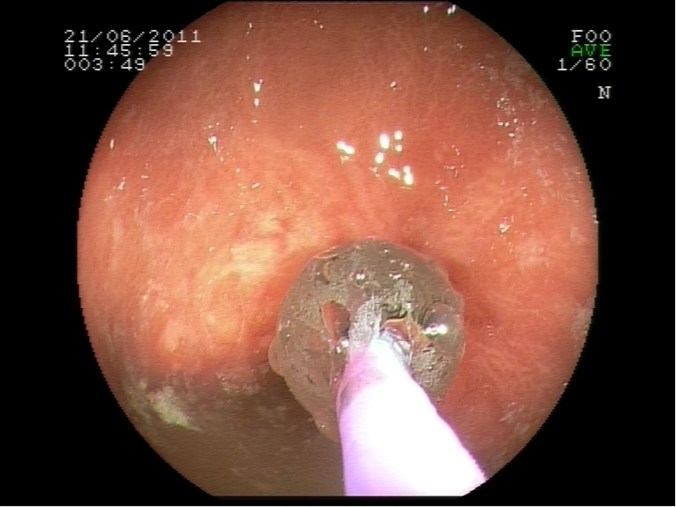

Dilatación de estenosis